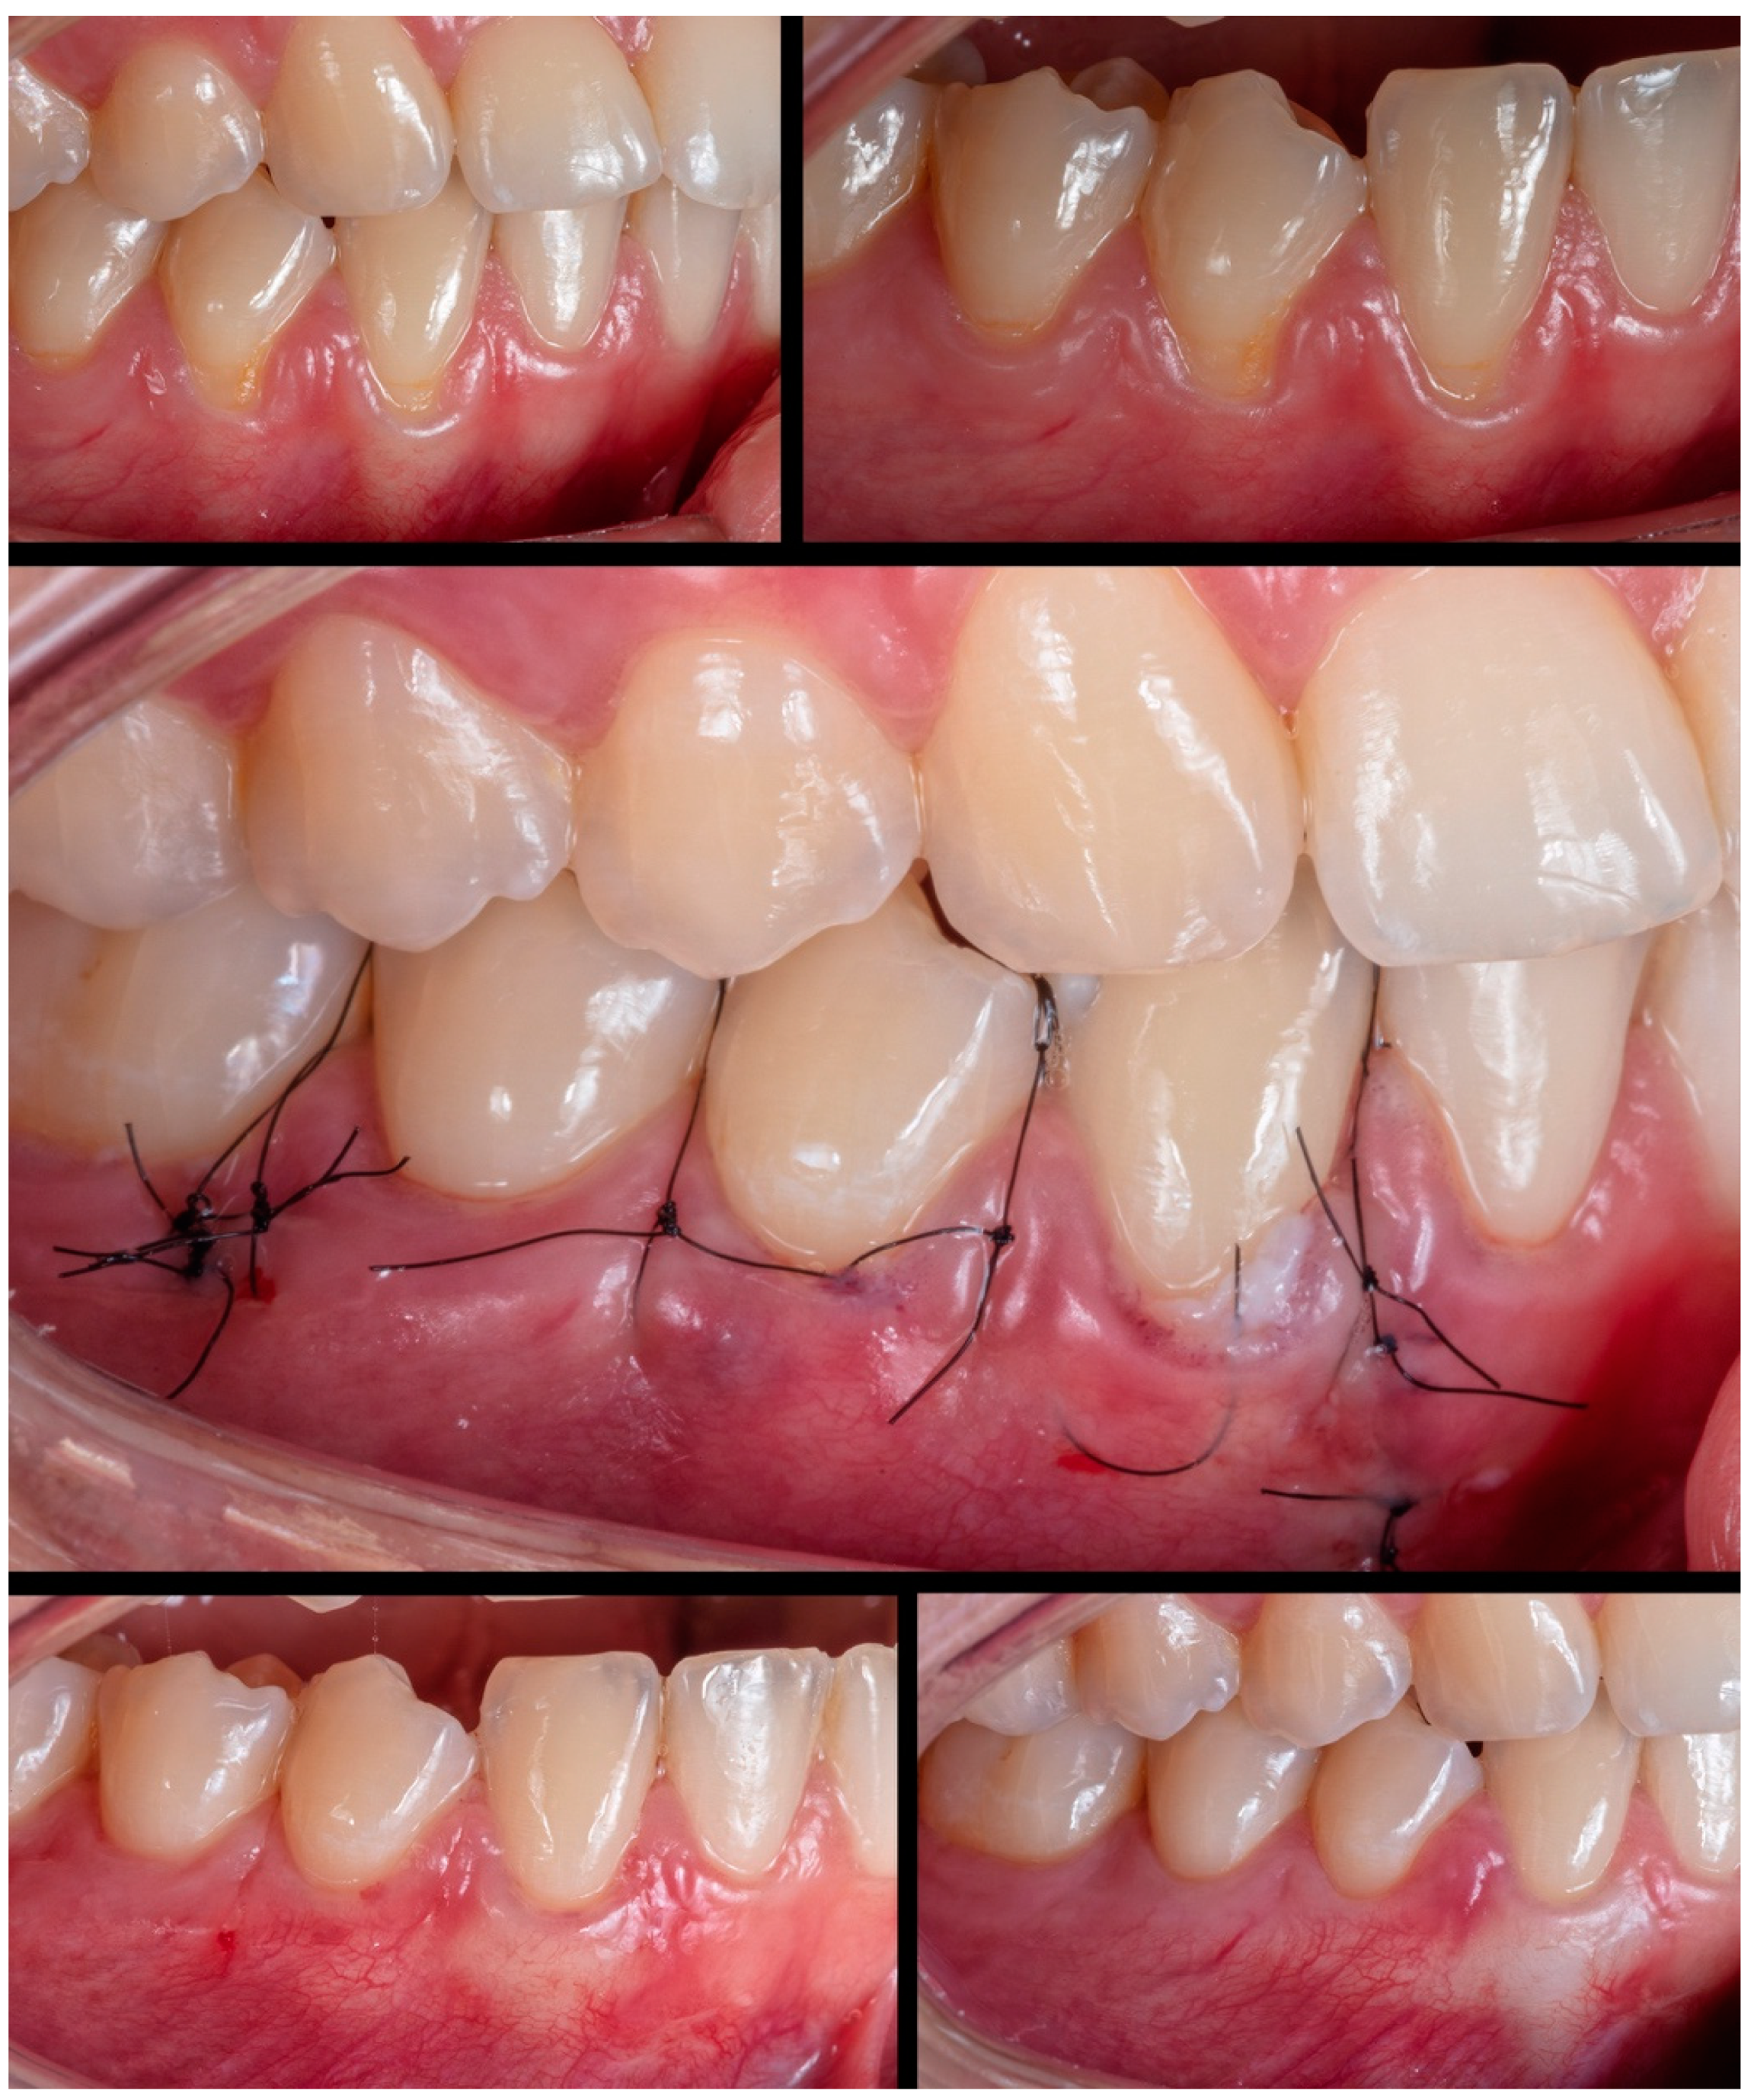

Case 4 presented GR in teeth #31 and #41, respectively, with 3mm and 1mm. The case was approached by applying two vertical incisions instead one in the distal of each involved tooth. The procedure and tissue manipulation happened without an event, and the result showed 100% RC (

Figure 5). Increasing the difficulty of the tissue management level, case 5 (

Figure 6) was done in a single tooth (#43), which was buccally positioned, classified as RT1, presenting 3mm of GR. Case performed yet in the anterior and buccal region of the mandible with one vertical incision. After MiTT, double-crossed suture was made to position the soft tissue coronally and keep it stable. After 7 days and 1 year, 100% for RC was reached, and a significant tissue volume was found. Another case (Case 6) was also done in that same region but with increased difficulty. Following toward the posterior region in the lower arch, 3 teeth had GR (#43-#45), respectively, with 1mm, 2mm, and 1mm. It was also found rotation in the premolars. MiTT was done with one vertical incision in the mesial site, and after 7, 14 days, and 1 year, there was 100% RC with no adverse event, even considering the mental nerve proximity (

Figure 7).

Figure 5.

Case 4 shows initial pictures of the GR defect (#41 and #31) and thin phenotype present; CTG over the receptor site with 2 distal vertical incisions to apply MiTT; suture performed; and the healing period after 6 months.

Figure 6.

Case 5 shows initial pictures of the GR defect (#43); a picture showing the final aspect immediately after surgery (double-crossed suture); and the healing period after 1 and 1 year.

Figure 7.

Case 6 shows initial pictures of the multiple GR defects (#43-#45); a picture showing the final aspect immediately after surgery (double-crossed suture); and the healing period after 1 and 6 months.